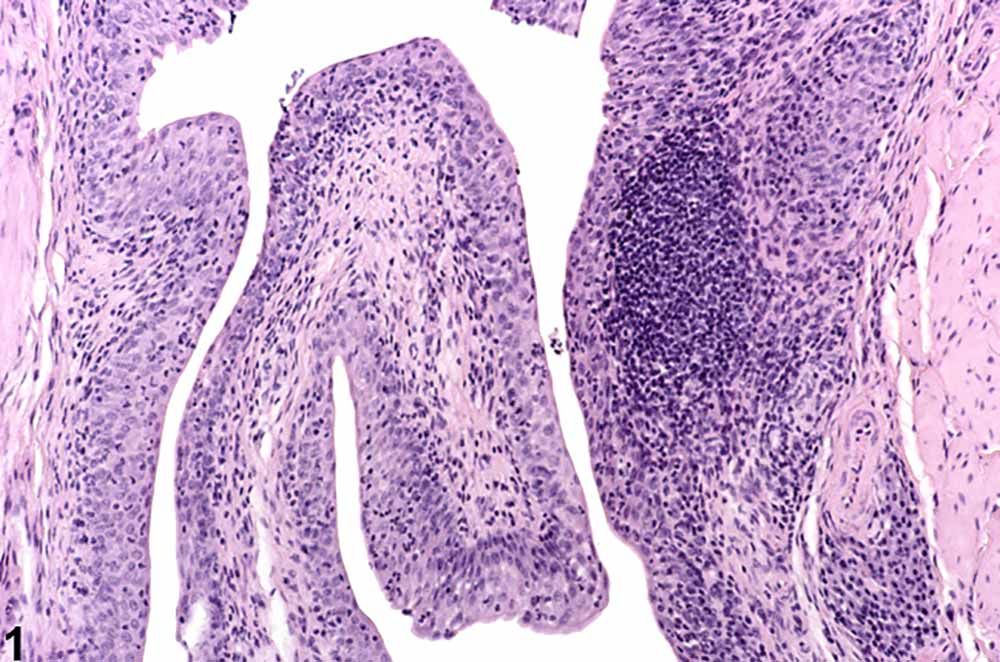

Slika: Vnetje mehurja.

Slika: Prerez stene mehurja.